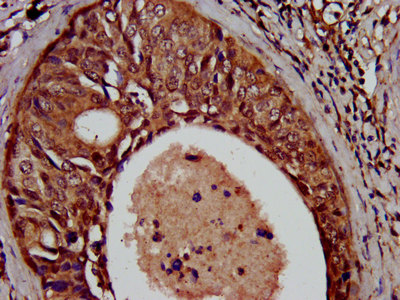

IHC image of CSB-PA883417LA01HU diluted at 1:500 and staining in paraffin-embedded human cervical cancer performed on a Leica BondTM system. After dewaxing and hydration, antigen retrieval was mediated by high pressure in a citrate buffer (pH 6.0). Section was blocked with 10% normal goat serum 30min at RT. Then primary antibody (1% BSA) was incubated at 4°C overnight. The primary is detected by a biotinylated secondary antibody and visualized using an HRP conjugated SP system.